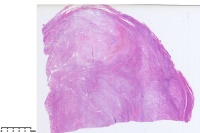

平滑肌瘤伴玻变、红色变性?

子宫肌瘤

平滑肌瘤伴透明变性,局部出血。